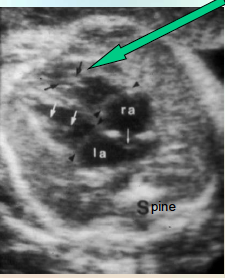

where is the moderator band? what is it?

the foramen ovale?

Moderator band (AKA septomarginal trabecula in right ventricle). thick muscle.

Foramen Ovale (thin white arrow pointing down)

can you identify the fetal lt/rt sides?

also note the lung echotexture

sp is spine in trans